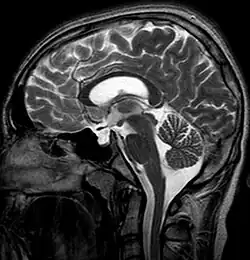

Das Empty-Sella-Syndrom (ESS; Syndrom der leeren Sella turcica) ist ein relativ häufiger neuroradiologischer oder pathologischer Befund, der häufig einer anatomischen Normvariante entspricht, aber auch eine hormonelle Erkrankung darstellen kann.

Die Sella turcica (deutsch: „Türkensattel“) stellt eine Schädelgrube mittig im Bereich der mittleren Schädelgrube (Fossa cranii media) dar, in der normalerweise die Hypophyse liegt, die zahlreiche Hormone bildet und damit Vorgänge wie Wachstum, Fortpflanzung und Stoffwechsel reguliert.

Beim Empty-Sella-Syndrom findet sich jedoch keine typische Form der Hypophyse in dieser Schädelgrube, sondern es kommt zu einer Hernien-artigen, von Liquor cerebrospinalis angefüllten Ausweitung des Subarachnoidalraums (Arachnoidozele) in die Sella turcica hinein. Dadurch wird die Hypophyse auf den Boden der Sella turcica gedrückt und erscheint wie „ausgewalzt“. Als Folge der Kompression der Hypophyse kann es zu endokrinen Störungen kommen.[1]